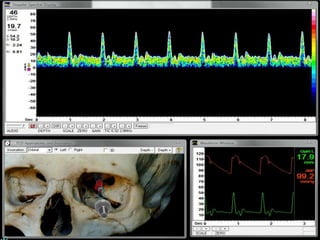

Alta resistencia-bajo flujo

Alta resistencia-alto flujo

Baja resistencia-Alto flujo

Baja resistencia-Bajo Flujo

Día 1: Hipertension Endocraneana Día 2: Hipertensión endocraneana

sin vasoespasmo con vasoespasmo

Craniectomía Decompresiva

DIA 1 HSA DIA 9 HSA DIA 14 HSA

Seguimiento vasoespasmo